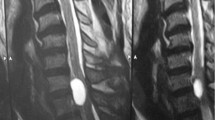

A 39-year-old female with an intraspinal extradural arachnoid cyst of the lumbar spine presented with intermittent radiating lumbar pain. The magnetic resonance imaging (MRI) showed a dorsal spinal extradural arachnoid cyst at L3/4. After wide laminotomy L3, operative cyst resection and stabilisation at L3/4 by posterior lumbar interbody fusion (PLIF), major symptom relief occurred.